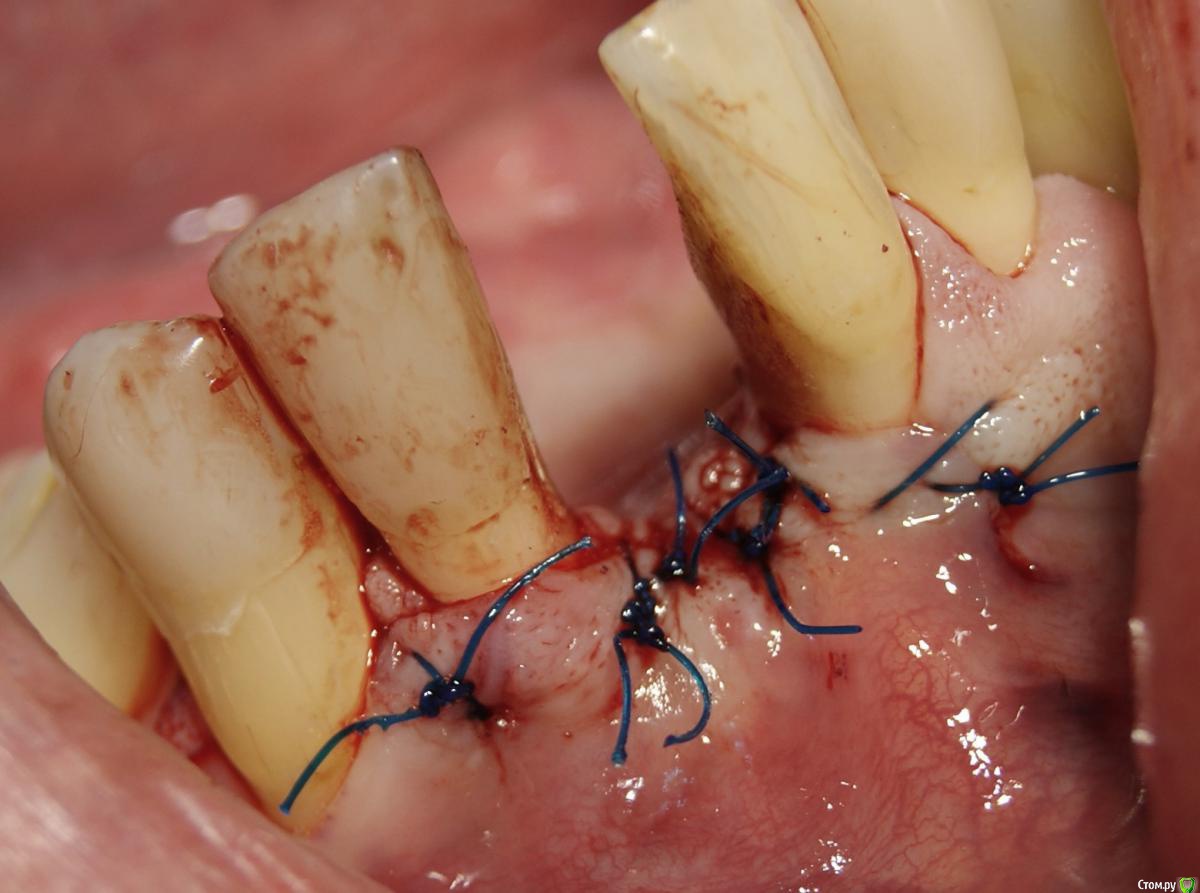

Jurai Опубликовано 25 декабря, 2016 Поделиться Опубликовано 25 декабря, 2016 *Предупреждение: фото на "мыльницу", не все этапы удались, но я работаю над этим) Вот пациент. Приятнейший, во всех отношениях, с негативным отношениям к мостовидным конструкциям. Полтора года лечил 41з по поводу периодонтита: толку не вышло. Удалил у широко известного многим стоматологам, особенно выпускам последних годов, доктора с ученой степенью. После удаления 4 месяца, по КТ область вполне достойно выглядит. Вот с чем пришел, обычное дело, все прилично: Раскрываю, а там между тонкими кортикалками мягко и упруго - резидуальная, фото нет. Открываю сильнее чем обычно, с расстройства не особо удачно. Кюретаж : Вид после, ушла вестибулярная кортикальная вместе с кистой: Сверлим 2,0, позиционердля рентген-контроля Имплантат ADIN UNP2,75Х11,5мм Ауто, джейсон коллагенфлис (что было под рукой) Швы. Контроль, перещелкивать не стали. В общем, понравился имплантат, для себя пометку кюретажить тщательнее, не надеяться, что организм все переварит. 1 9 Ссылка на комментарий